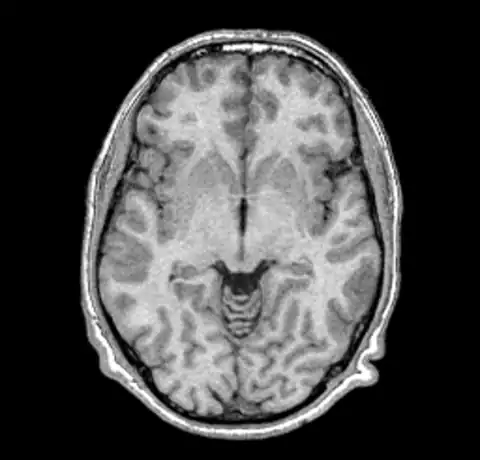

Note that it is difficult to pick the non-uniformity in the image unless you look carefully at the intensity of the white matter in the lower parts of the image. In order to correct this image we run nu_correct with the default parameters.

nu_correct original.mnc out.mnc

We can now take a look at the corrected file (out.mnc)

As it is very hard to pick the differences between the original and corrected version we can create a field image to visualise the differences.